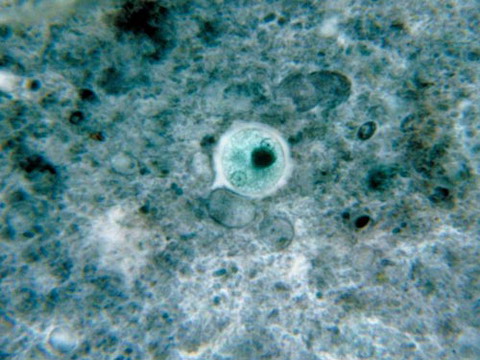

Ký sinh trùng Toxoplasma gondii: Loài ký sinh trùng hình lưỡi liềm này thường xâm nhập vào hệ thống thần kinh trung ương của con người. Con người bị nhiễm chúng do ăn thịt chưa nấu chín hoặc do tiếp xúc với phân mèo bị nhiễm bệnh. Hầu hết mọi người đã tiếp xúc với ký sinh trùng này một lần và sinh ra kháng thể miển nhiễm với nó. Nhưng một vài cá nhân có hệ miễn dịch yếu và cả bào thai có thể bị ảnh hưởng nghiêm trọng dẫn đến tử vong do nhiễm bệnh... Triệu chứng nhiễm: cúm, sốt, ớn lạnh, mệt mỏi, đau đầu.